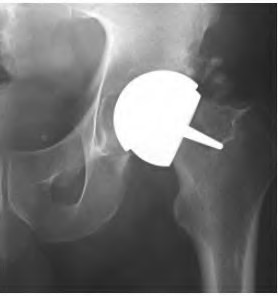

A 75-year-old man underwent total hip arthroplasty 10 years ago. He now reports mild groin pain which has been increasing lately. What is the most likely explanation for the finding in Figure A indicated with the arrows?

Osteolysis of the pelvis is a common complication associated with total hip arthroplasty. Osteolysis affects sockets with and without cement, and has been attributed to the biologic reaction to wear debris. With well-fixed cementless sockets, an expansile pattern of osteolysis is usually seen.

The radiographic appearance has a radiolucent area that starts at the implant-bone interface and expands into the cancellous bone away from the implant.

This pattern of osteolysis can be explained with the concept of effective joint space. This concept states that joint fluid and wear particles will flow according to pressure gradients and follow the path of least resistance.

The Level 5 review article by Chiang discusses osteolysis in further depth.